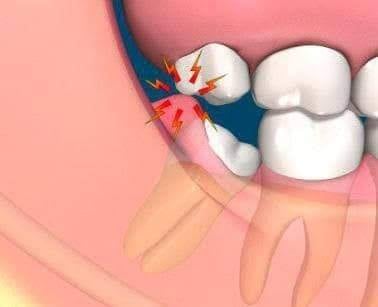

あごが小さく、親知らずの生えるスペースがない場合、横向きに生え、あごのなかに埋まってしまいます(埋伏智歯)。

横向きに倒れて生えている親知らずにはさまざまなリスクがあるので抜歯が必要かどうか、歯科医師に相談しましょう!

1.親知らずの周りの歯ぐきが腫れ、歯を支える骨まで溶けてしまいます(智歯周囲炎)。

また、放置すると痛みや腫れを繰り返し、悪化すると顔やのどのほうまで腫れ、口が開かなくなったり熱が出ることがあります(蜂窩織炎)。